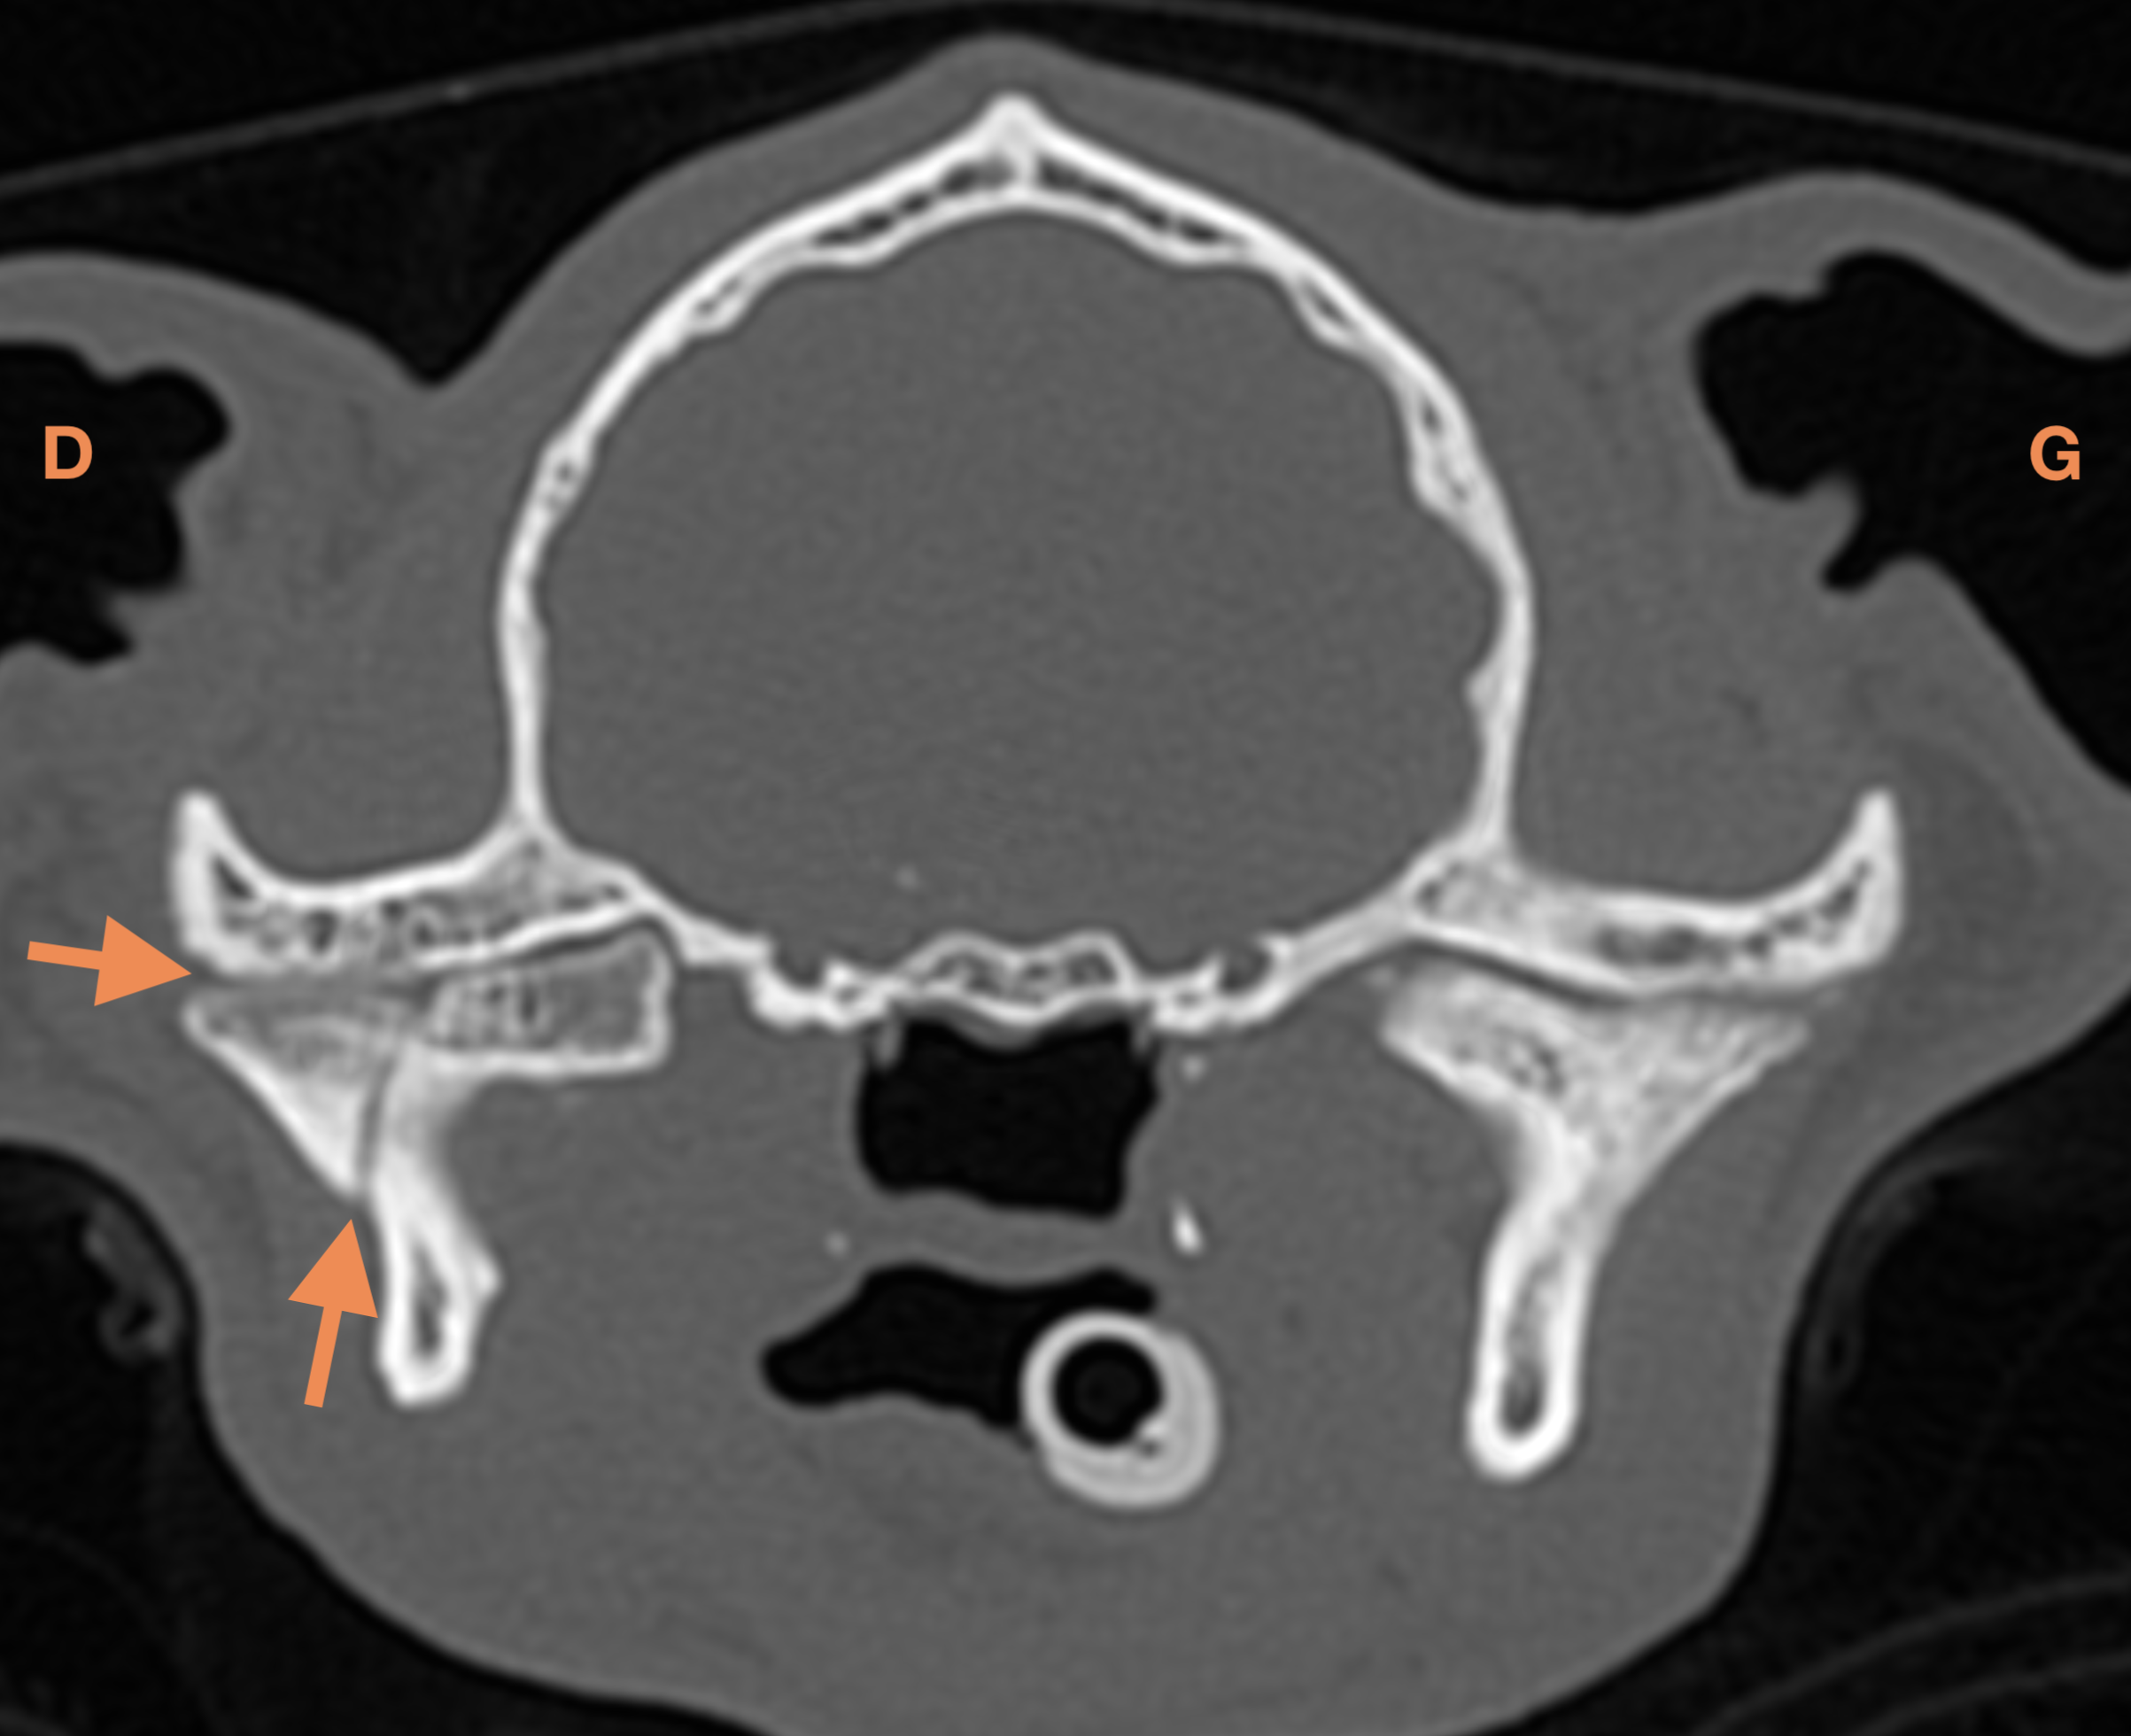

Examens complémentaires

L’examen tomodensitométrique met en évidence une persistance de la fracture articulaire peu déplacée du processus condylaire de la mandibule droite et l’apparition d’une réduction de l’interligne articulaire temporo-mandibulaire évoquant une incongruence articulaire, non visualisée deux mois auparavant. De multiples fractures peu déplacées des structures osseuses de la face et du nez persistent, à l’origine d’une déviation à gauche du massif nasal. Enfin une lésion de fibrose cicatricielle du muscle masséter droit est mise en évidence en regard de l’aire de passage du nerf facial.

Diagnostic